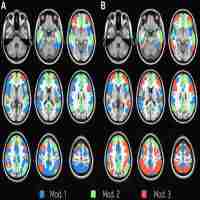

| Abstract | Previous studies have rarely examined how temporal dynamic patterns, event-related coherence, and phase-locking are related to each other. This study assessed reaction-time-sorted spectral perturbation and event-related spectral perturbation in order to examine the temporal dynamic patterns in the frontal midline (F), central parietal (CP), and occipital (O) regions during a chemistry working memory task at theta, alpha, and beta frequencies. Furthermore, the functional connectivity between F-CP, CP-O, and F-O were assessed by component event-related coherence (ERCoh) and component phase-locking (PL) at different frequency bands. In addition, this study examined whether the temporal dynamic patterns are consistent with the functional connectivity patterns across different frequencies and time courses. Component ERCoh/PL measured the interactions between different independent components decomposed from the scalp EEG, mixtures of time courses of activities arising from different brain, and artifactual sources. The results indicate that the O and CP regions' temporal dynamic patterns are similar to each other. Furthermore, pronounced component ERCoh/PL patterns were found to exist between the O and CP regions across each stimulus and probe presentation, in both theta and alpha frequencies. The consistent theta component ERCoh/PL between the F and O regions was found at the first stimulus and after probe presentation. These findings demonstrate that temporal dynamic patterns at different regions are in accordance with the functional connectivity patterns. Such coordinated and robust EEG temporal dynamics and component ERCoh/PL patterns suggest that these brain regions' neurons work together both to induce similar event-related spectral perturbation and to synchronize or desynchronize simultaneously in order to swiftly accomplish a particular goal. The possible mechanisms for such distinct component phase-locking and coherence patterns were also further discussed. |